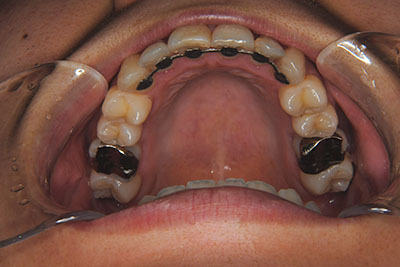

おとなの方でも矯正治療をあきらめないでください!

いくら歯が動き易くとも、本人がやる気でなければ効果は出ませんし、むし歯発生のリスクも高まります。おとなの方は顎の成長が終わっているため、治療の計画が立てやすいとも言えます。「もう大人だから…」とあきらめず、一度ご相談ください。